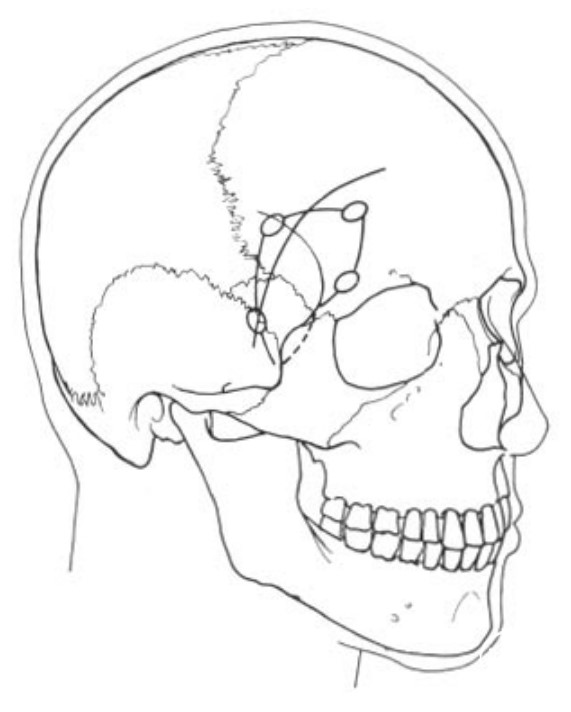

眶上外侧入路更靠近颞部,骨窗1/3位于颞上线以上,2/3位于颞上线以下(Romani R, 2009年)。

额外侧入路的皮肤切口和骨瓣。

额外侧入路的艺术家视图。可见:额外侧入路是从前颅底外侧进入鞍区,并非直接沿着蝶骨嵴、外侧裂进入。